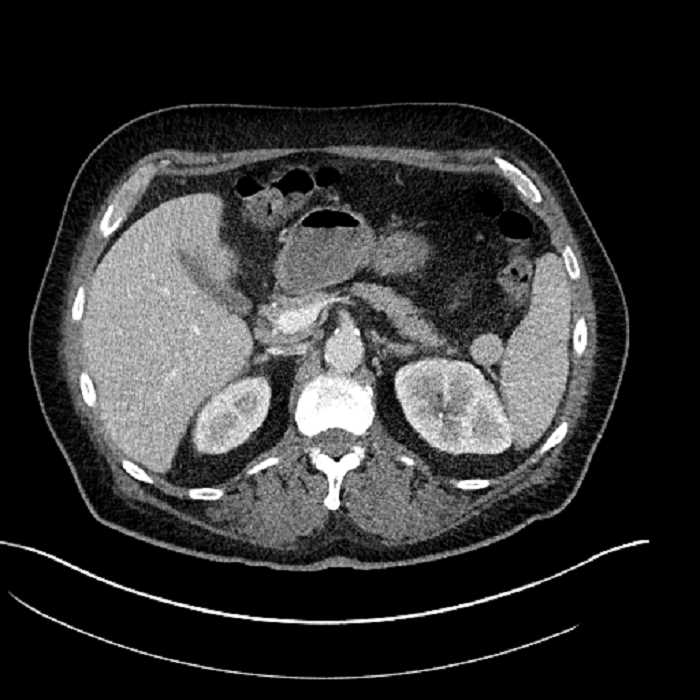

Age: 63

Sex: Male

Indication: Abdominal pain

• Large fluid density structure in hepatic segments 7 and 8 measuring 10 x 7 x 7 cm with internal septation and circumferential ill-defined low density compatible with edema

• Peripherally enhancing subcapsular collections along the anterior margin of the left hepatic lobe measuring 3 x 1 cm and 2 x 1 cm

• Clearly marginated fluid density structure in segment 7 and several other scattered tiny hypodensities, which likely represent cysts

• Hepatic abscess

Acute sigmoid diverticulitis complicated by a small contained perforation and a large abscess in the right hepatic lobe. Additional small subcapsular abscesses along the anterior margin of the left hepatic lobe.

• The classic CT imaging appearance is a double target sign with internal low density surrounded by an internal enhancing rim (capsule) and a low density external rim (edema)

Hepatic abscess showing the double target sign with low density internally surrounded by a thin inner enhancing rim (red arrow) and ill-defined outer low density rim (yellow arrow). Blue arrow indicates an internal septation. Red arrows: additional smaller subcapsular abscesses. Red arrow: focal contained perforation associated with diverticulitis.